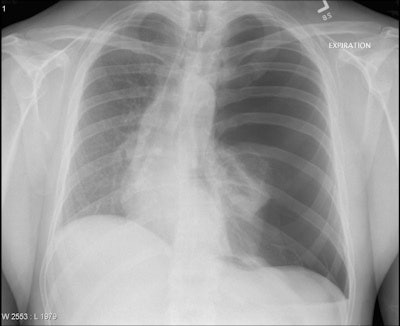

The survey included nine hypothetical clinical vignettes, each associated with a chest x-ray that showed only a single acute chest pathology. For example, a vignette for a patient with dyspnea and pleuritic chest pain contained a classic image of pneumothorax. The researchers further added a low-risk vignette associated with a normal chest x-ray. They asked participants to read each of the 10 vignettes, look at the chest x-rays, and type in the pathology they believed they saw. Also, they asked them to state their confidence in the diagnosis and indicate any prior exposure to the topics.

Overall, the highest rate of correct diagnosis was for diaphragmatic herniation (77%), followed by pneumoperitoneum (67%) and pneumothorax (54%). The lowest rate of correct diagnosis occurred for acute respiratory distress syndrome (ARDS) (8%), foreign body (12%), and the low-risk vignette associated with the normal chest x-ray (15%). The key findings are shown on the table below.

Pneumothorax | 54 | 19 | 54 |

Tension pneumothorax | 33 | 18 | 45 |